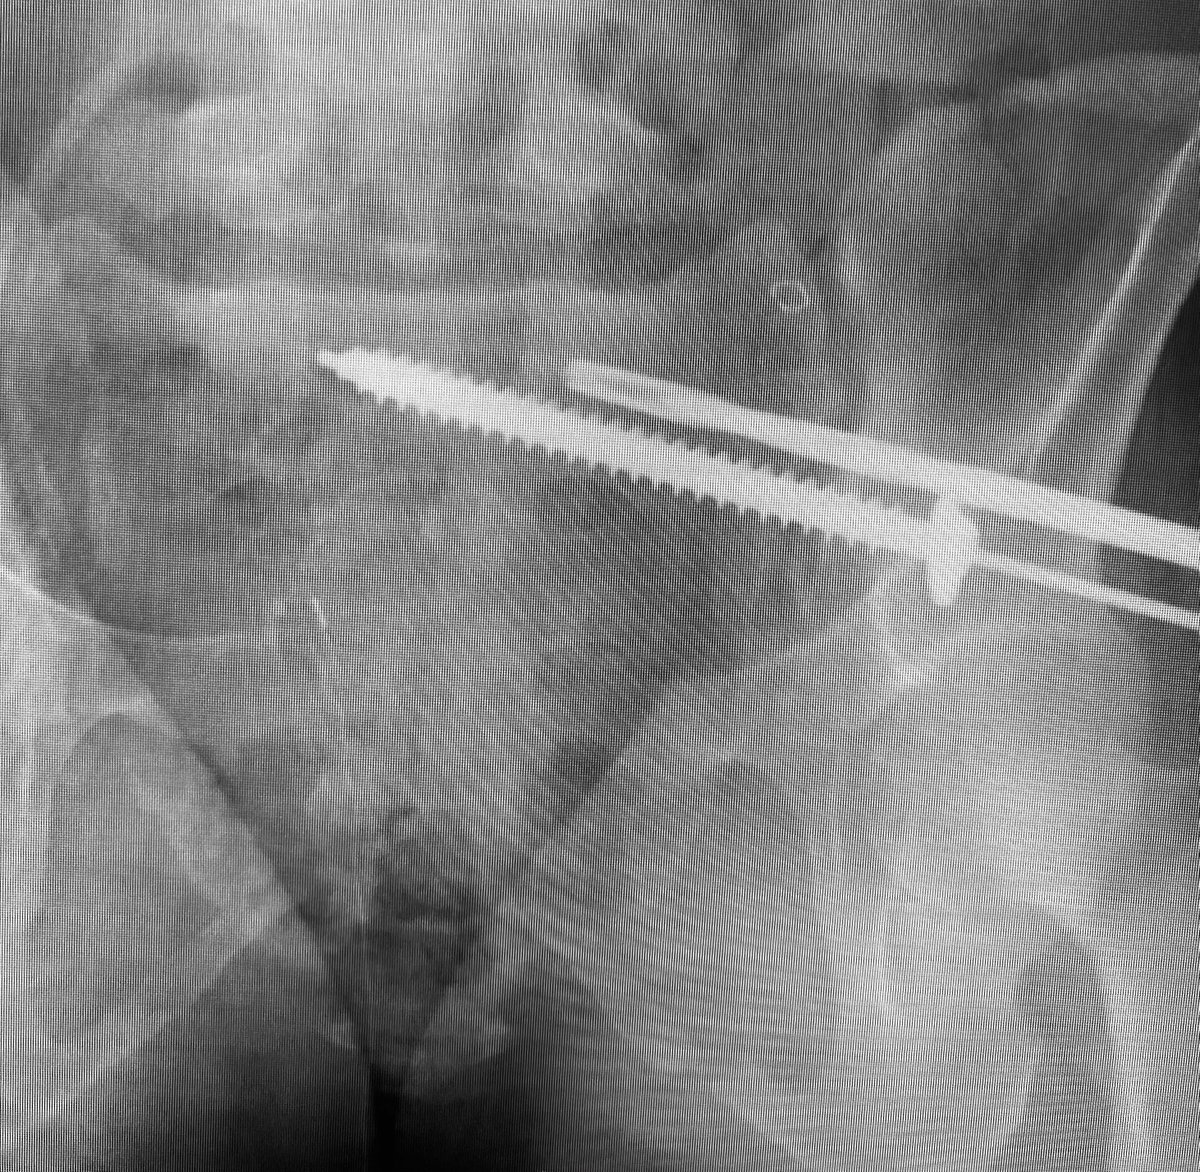

Control your iliosacral screw insertion precision by using an initial K wire to simply identify the optimal insertion site for your intended pathway-insert it 1-2cms then proceed directly to using the cannulated drill - the drill allows early slight corrections without deformity

Use the cannulated drill to avoid wayward misdirections from more flexible guide wires